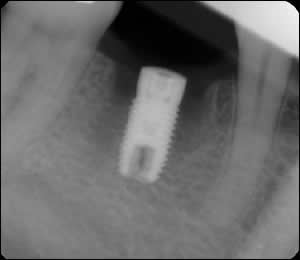

Fig 3: A dental implant was placed in the interseptal bone of the extraction site.